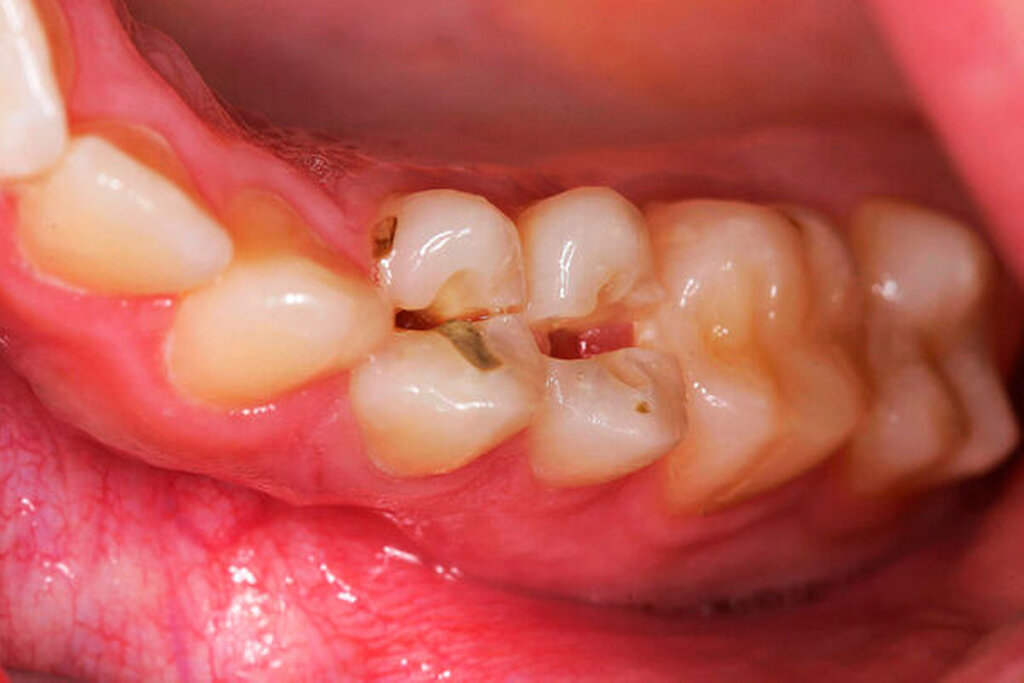

Der extraorale Befund war bis auf ein Hämatom im Kinnbereich unauffällig. Eine Kiefergelenksfraktur wurde bereits am Vortag im unmittelbar nach dem Unfall aufgesuchten Klinikum Ludwigshafen ausgeschlossen. Intraoral zeigte sich ein vollständiges, kariesfreies Gebiss mit Z. n. abgeschlossener kieferorthopädischer Therapie. Die Zähne 14 und 15 hatten einen Lockerungsgrad II sowie eine alio loco angebrachte flexible SÄT-Drahtschienung. An den Zähnen 16, 26, 45 und 46 wies die Patientin z. T. ausgedehnte Schmelz-Dentin-Abscherungen auf. Nach Entfernung der Schienung 14 Tage später zeigten sich die komplizierten Kronen-Wurzel-Frakturen an 14 und 15.

Versorgung der Zähne 16, 26, 45 und 46 mit Compositfüllungen